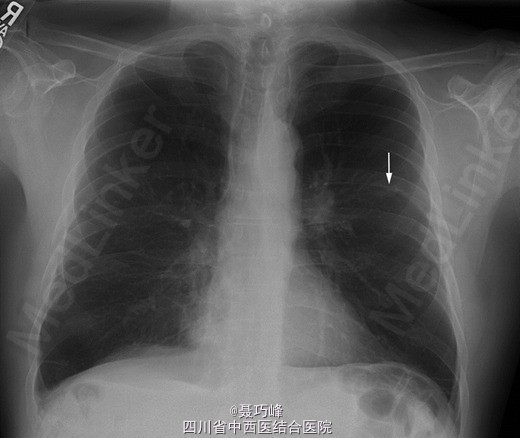

患者胸部、心脏和腹部体检结果均正常。面部、头皮、颈部、肩部及四肢有紫红色皮疹,伴随多处浅表性溃疡。患者眼睑处也有紫红色皮疹,伴眶周水肿。(图1) 双手的近端指间关节,特别是中指和无名指,存在红斑;甲周(特别是无名指)存在弥漫红斑(图 2)。甲周处存在毛细血管扩张。肌肉骨骼检查显示有双臂和双腿轻度近端肌肉无力。其他检查结果均为阴性。 CBC 计数、肾功能和电解质水平正常。异常实验室检查结果如下:天门冬氨酸转氨酶:124U/L,丙氨酸转氨酶:53U/L,肌酸激酶:1952U/L。胸片显示:左上叶小结节不透亮影(图 3)。